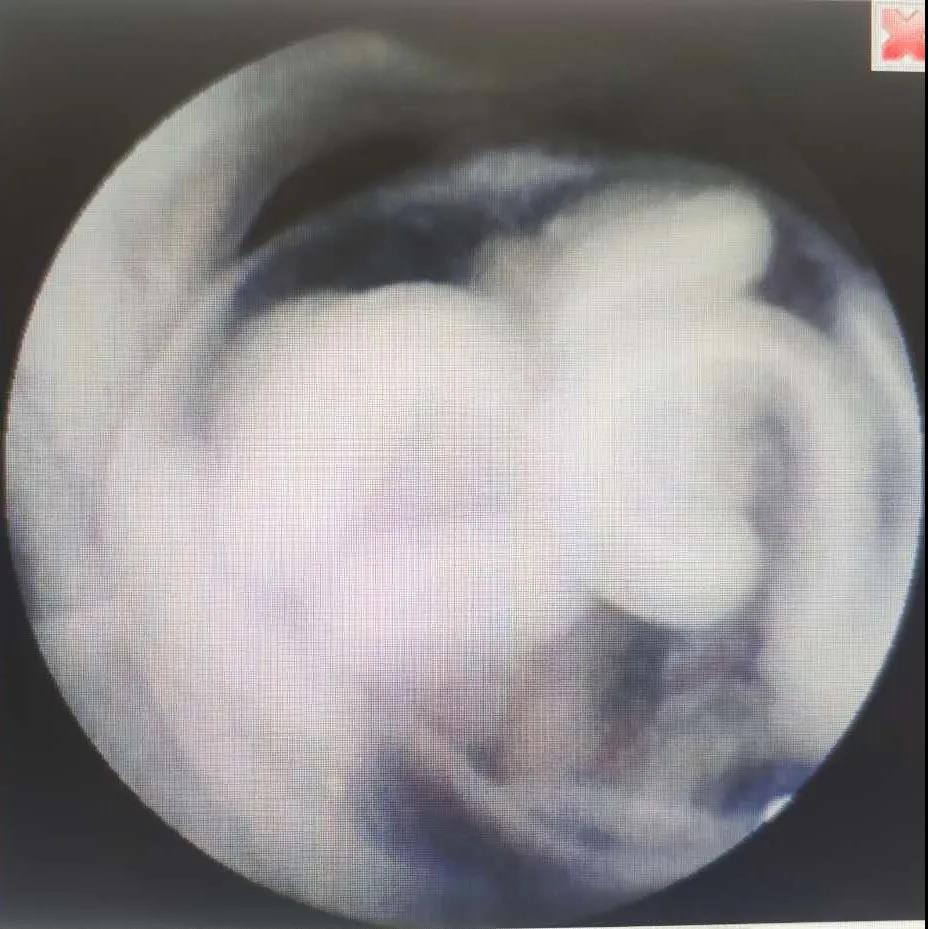

现在的“宫腔直视吸引手术系统”

观察与吸引同步,

每一步都清晰可见!

通过在吸引管前置超微型高分辨率摄像头,将图像传输和吸取通道集成在同一根管上,临床工作人员通过摄像头近距离的探视宫腔内组织,对宫腔组织进行直观观察,清晰分辨,准确定位,定点吸附。

全程直视,观察与吸引同步,医生通过摄像头近距离探视,清晰分辨。

OMOM直视下小月份胚胎组织